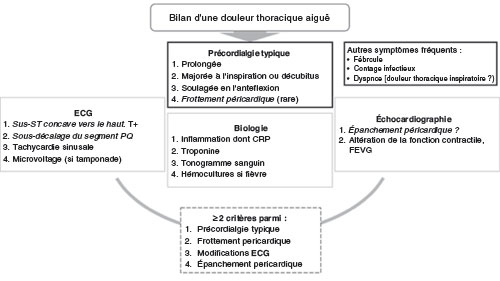

I Diagnostic

Le diagnostic de péricardite aiguë est évoqué dans le contexte d’une douleur thoracique aiguë. Les diagnostics différentiels (syndrome coronarien aigu, embolie pulmonaire et dissection aortique) doivent toujours être évoqués car ils sont grevés d’une morbimortalité importante. Le diagnostic de péricardite se pose devant l’association d’une douleur thoracique évocatrice, d’un éventuel frottement péricardique, de modifications ECG typiques et d’un épanchement péricardique. La présence de deux de ces critères est nécessaire pour confirmer le diagnostic. La réalisation d’un ECG et d’une échocardiographie est donc systématique.

La démarche diagnostique après évocation d’une péricardite est présentée figure 20.4.

Fig. 20.4. ![]() Démarche diagnostique après évocation d’une péricardite.

Démarche diagnostique après évocation d’une péricardite.